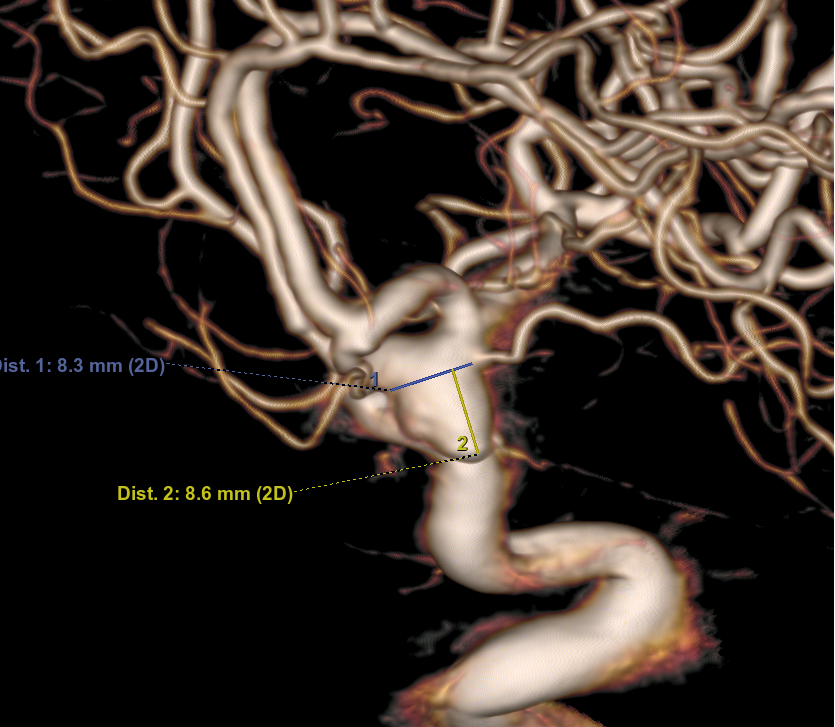

榕山镇70岁的胡婆婆因突发头颈部疼痛入住我院。急诊头颅CT显示广泛蛛网膜下腔出血,经验丰富的神经外科医生立即意识到是可怕的颅内动脉瘤破裂出血。经过脑血管造影检查证实,果然是右侧后交通动脉瘤破裂出血

图片

情况更加复杂的是,动脉瘤体大、瘤颈宽、形态不规则,随时都有再次破裂出血的危险。胡婆婆年龄较大,身体瘦弱,基础条件差,开颅手术耐受能力极差。在充分评估病情与患者家属深入沟通后,科室一致决定为胡婆婆进行微创手术。

神经外科介入团队迅速启动绿色通道手术预案,由侯黎明主任医师与汪棋笙副主任医师主刀,在李华国主治医师协助下行了微创颅内动脉瘤支架辅助介入栓塞术。经过数小时手术,成功栓塞了动脉瘤,解除了再次出血风险。